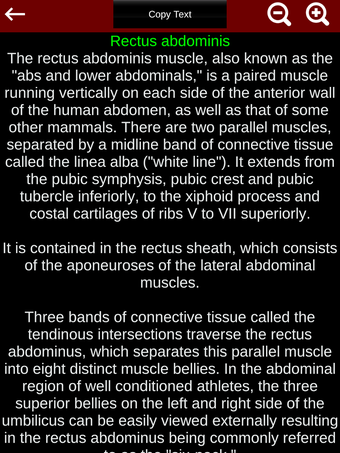

Esta herramienta educativa proporciona una descripción de cada músculo del cuerpo humano, así como un modelo tridimensional del sistema muscular. Con sólo tocar con el dedo, la aplicación revelará la información pertinente.

Los usuarios pueden hacer zoom sobre el músculo, así como elegir si ocultar o mostrar los datos. La orientación puede ser horizontal o vertical, según convenga más.